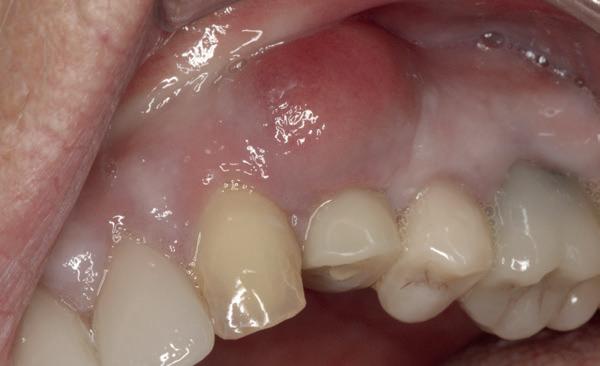

Het kantelpunt: de patiënt komt terug (afbeelding 14-16)

De patiënt meldde zich opnieuw in de praktijk met klachten: pijn, zwelling en een duidelijke intraorale infectie. Bij inspectie zag ik direct een probleemhet ging om een klassiek beeld van peri-implantair botverlies met een abces. Dit patroon van botverlies en infectie spiegelde sterk de gevolgen van thermische trauma.

Op de röntgenfoto’s zag ik wat ik al vreesde: er was botresorptie rond het implantaat. De zachte weefsels waren ontstoken en het implantaat vertoonde teke-

nen van mobiliteit. Op dat moment wist ik precies wat er was misgegaan.

Dit was geen kwestie van een verkeerde occlusie of een slecht gekozen abutment. Dit was een puur biologisch probleem, veroorzaakt door mijn onderpreparatie van de osteotomie en de daarmee gepaard gaande botnecrose of compressie. Mijn streven naar immediaat belasten had me verblind, en ik had een fundamentele regel van de implantologie genegeerd: bot moet kunnen ademen. Op dat moment had ik geen andere keuze dan de situatie te herstellen.

Herstel: terug naar de basis (afbeelding 17-19)

De behandeling van dit mislukte implantaat volgde een stapsgewijze aanpak:

1. Explantatie van het implantaat. Het implantaat werd voorzichtig verwijderd, waarbij ik probeerde zoveel mogelijk bot te behouden.

2. Curettage en reiniging. De alveole werd intensief gecuretteerd en gespoeld tot er geen exsudaat meer aanwezig was. Met goede communicatie kon ik de patiënt overtuigen om 3 maanden later terug te komen voor de botopbouw, zodat we het beste fundament konden creëren voor een duurzame oplossing.